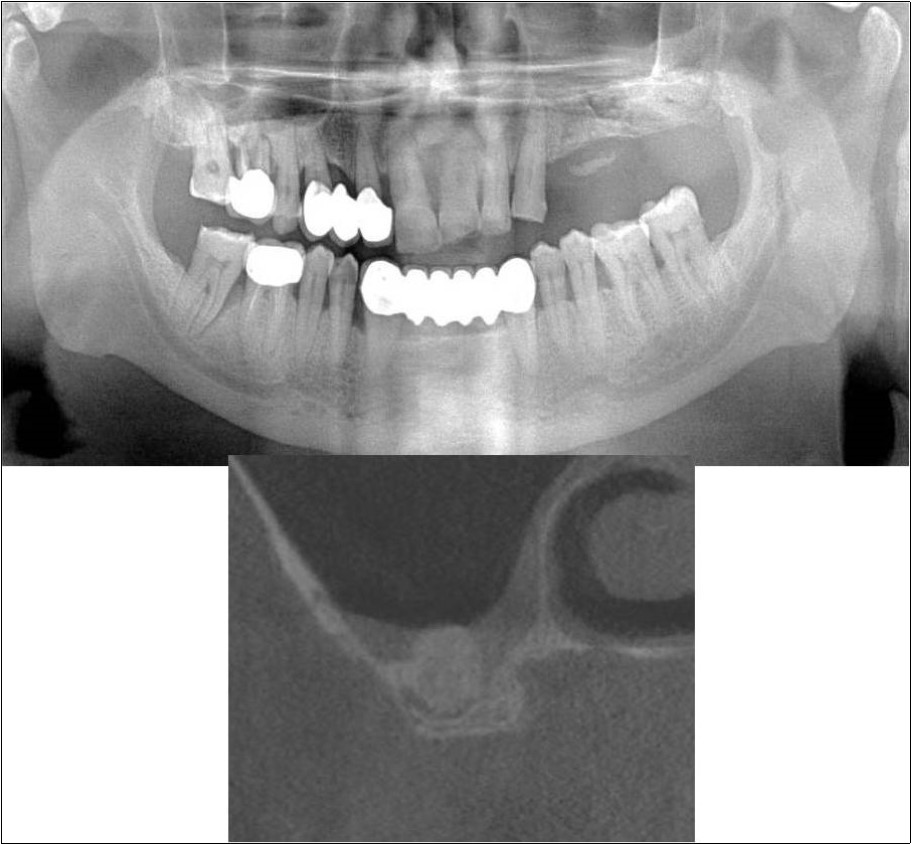

Case Report 2:

A 42 years old male patient reported to the Department of Oral and Maxillofacial Surgery, D.A.P.M.R.V Dental College and Hospital with a chief complaint of inability to chew food because of missing teeth in upper right and left back tooth regions from past one year. The teeth were extracted an year ago because of gross loss of tooth structure and poor prognosis for root canal treatment. Patient was a hypertensive since 4 years and was on medication for the same. Patient did not give history of any existing sinus pathologies. All possible rehabilitative options were explained to the patient and a treatment plan of replacement of missing teeth with implant supported prosthesis using one dental implant in 17 region was finalized.

Clinical and Radiological Assessment:

1.Partially edentulous maxillary and mandibular arches with missing 17, 26, 45, 46;

2.Increased pneumatisation of right maxillary sinus;

3.Height of available bone- 6.6mm;

4.Transverse thickness of available bone (CBCT evaluation)- 11mm;

5.Inter-ridge space adequate to place implant (10mm).

Treatment:

Patient underwent the procedure of indirect sinus elevation using sinus osteotomes in relation to 17 region. Calcium phosphosilicate putty was dispensed as the graft material through the crestal osteotomy site to maintain the elevated sinus membrane followed by placement of a dental implant measuring 5 x 10mm under local anaesthesia and strict aseptic protocols .The implant was allowed to osseo-integrate for a period of six months during which the patient was followed-up periodically and was assessed for peri-implantitis, crestal bone loss and mobility. At the end of 6 months, a repeat CBCT scan was advised to evaluate the increase in bone height. (Figure 9a,b, pre-treatment; Figure 10a,b, post-treatment)

Figure 9.(a,b) Pre-treatment OPG and cross section of CBCT showing residual alveolar bone height for Case No.2

Figure 10.(a,b) Post-treatment OPG and cross section of CBCT showing residual alveolar bone height for Case No.2